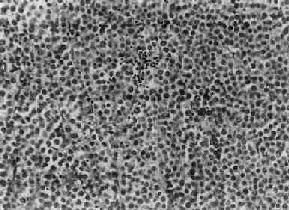

图14-1 精原细胞瘤 瘤细胞大、胞浆透明,核大,核仁明显,间质内有淋巴细胞浸润 少数精原细胞瘤的实质细胞大小不一,核粗大,分裂像较多,称为分化不良性或未分化性精原细胞瘤(anaplastic seminoma);另有少数精原细胞瘤的瘤细胞形态似不同成熟程度的精母细胞,称精母细胞型精原细胞瘤(spermatocytic seminoma),后者预后较好。 本瘤对放射治疗高度敏感。淋巴道转移较常见,血道转移较少发生。

一、精原细胞瘤精原细胞瘤(seminoma)起源于睾丸原始生殖细胞,为睾丸最常见的肿瘤,多发生于中年以后,常为单侧性,右侧略多于左侧。发生于隐睾的机率较正常位睾丸高几十倍。本瘤为低度恶性。 肉眼观,睾丸肿大,有时可达正常体积的10倍,少数病例睾丸大小正常。肿瘤体积大小不一,小者仅数毫米,大者可达十余厘米,通常直径为3~5cm。由于睾丸白膜比较韧厚,未被肿瘤破坏,故通常睾丸的原来轮廓尚保存。切面瘤组织呈淡黄或灰黄色,实体性,均匀一致如鱼肉,其中往往可见到不规则坏死区。镜下,典型的精原细胞瘤有瘤细胞形态结构单一和间质内有淋巴细胞浸润两个特征,(图14-1)。瘤细胞弥漫分布或呈索状结构,细胞的形态一致,与正常精小管内精原细胞相似,瘤细胞大,圆形或多角形、境界清楚、胞浆透明,核大、位于中央,核膜及染色质较粗,有1~2个嗜酸性核仁,核分裂像不多见。间质为纤细的纤维组织或致密的胶原纤维,其中有多少不等的淋巴细胞浸润,有时可有淋巴滤泡形成。